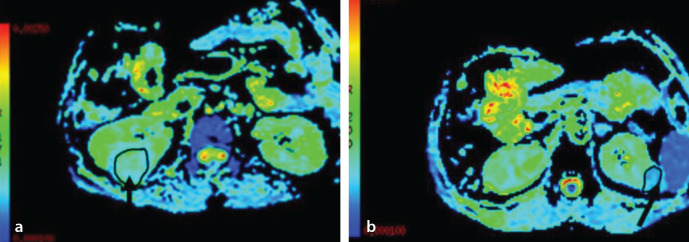

Methods: Sixty-eight patients with ccRCC and 18 patients with RAMF were retrospectively studied. For DKI and apparent diffusion coefficient (ADC), respiratory-triggered echo-planar imaging sequences were acquired in the axial plane (three b-values: 0, 1000, 2000 s/mm2; one b-value: 2000 s/mm2). Mean diffusivity (MD), fractional anisotropy (FA), mean kurtosis (MK), kurtosis anisotropy (KA), radial kurtosis (RK), and ADC were evaluated. The diagnostic efficacy of various diffusion parameters in predicting ccRCC and RAMF was compared.

Results: The ADC and MD values of ccRCCs were higher than those of RAMFs (P < 0.05), whereas comparable FA, MK, and KA values were observed between ccRCCs and RAMFs (P > 0.05). Moreover, the RK values of RAMFs were higher than those of ccRCCs (P < 0.05). Receiver operating characteristic (ROC) curve analyses showed that MD values had the highest diagnostic efficacy in differentiating ccRCCs from RAMFs. In pairwise comparisons of ROC curves and diagnostic efficacy, DKI parameters demonstrated better diagnostic accuracy than ADC in differentiating between ccRCCs and RAMFs (P < 0.05).